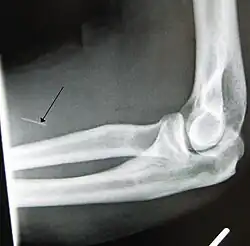

- Arterial damage – Arterial pseudoaneurysms may form at injection sites, which can rupture, potentially resulting in hemorrhage, distal ischemia, and gangrene. Inadvertent intra-arterial injection can also result in endarteritis and thrombosis, with ultimately similar consequences.[3]